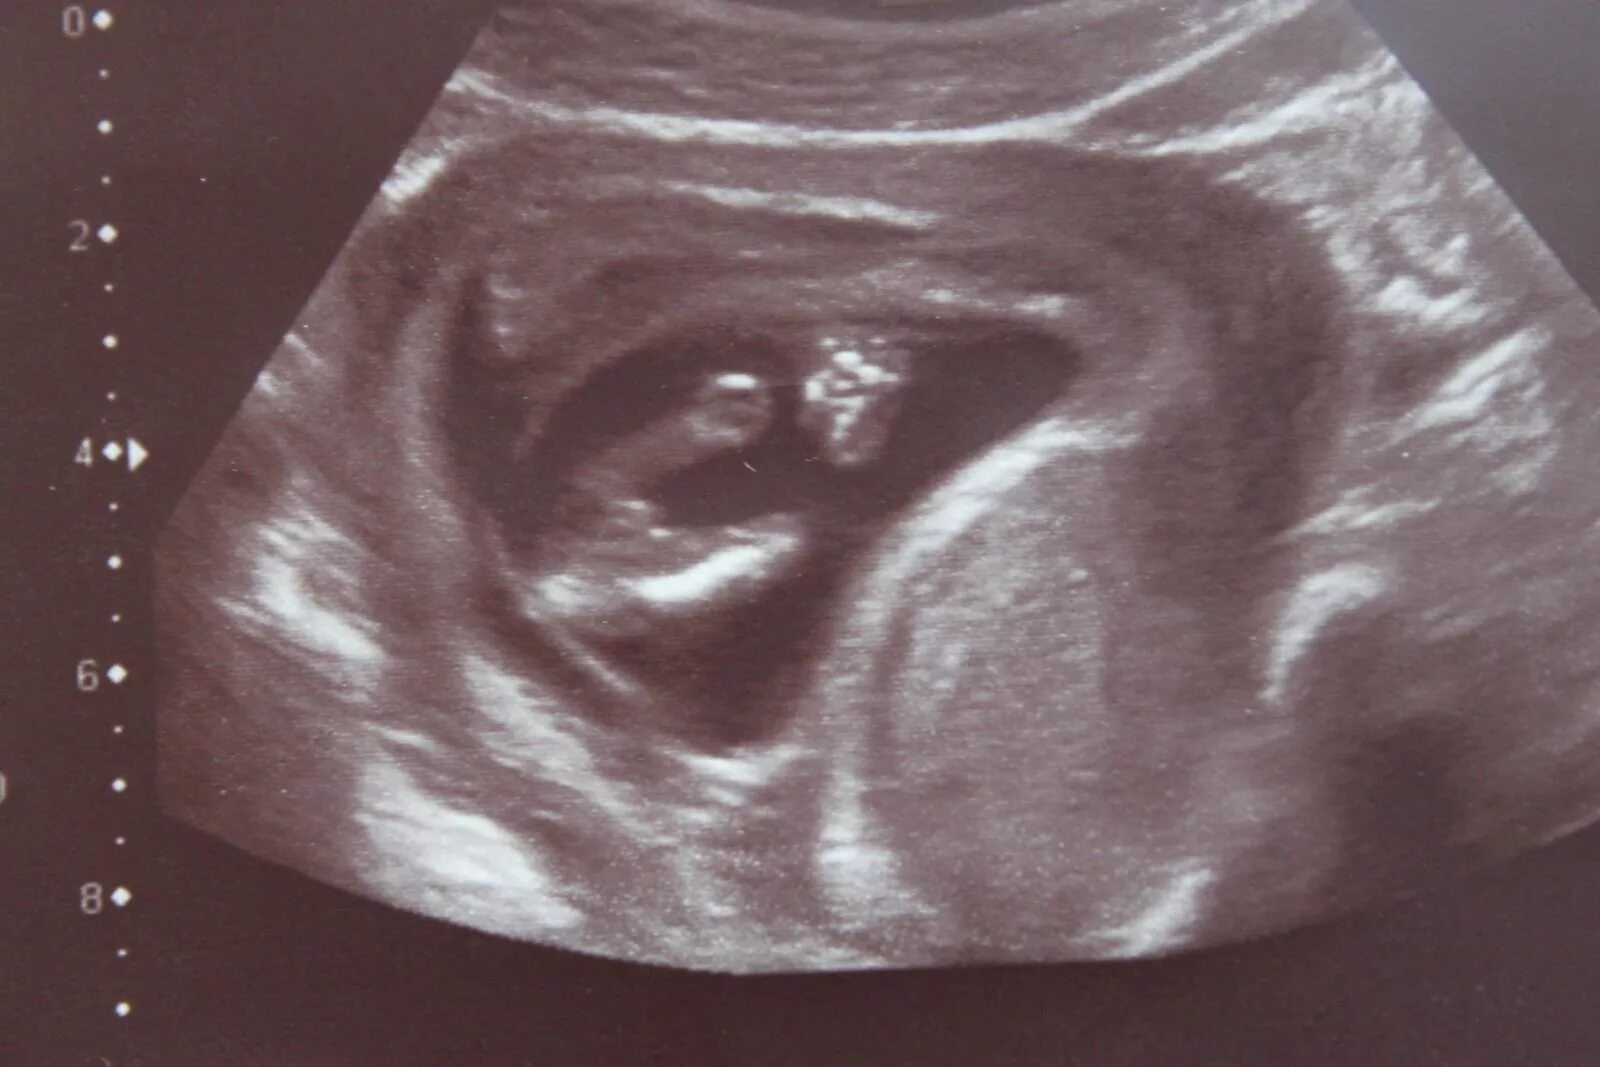

Ребенок в 13 недель